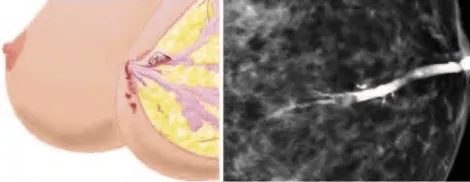

Phần tiêu đề “Cận lâm sàng”Hình ảnh “(Trái) Sơ đồ vị trí u nhú gây tiết dịch máu. (Phải) Chụp cản quang ống tuyến vú cho thấy hình ảnh u nhú trong ống”.

Siêu âm:

- Ba dạng hình ảnh: Trong ống tuyến (đường ống giãn có khối nội dịch), trong nang (khối trong khối nang), hoặc dạng đặc (khối ranh giới rõ).

- Nếu khối quá nhỏ, chỉ thấy ống dẫn sữa giãn.

Nhũ ảnh: Thường không thấy khối rõ ngoại trừ trường hợp kích thước lớn. Nếu có, khối nhỏ, bờ rõ, có thể có vôi hóa vi thể nhẹ.

Chụp cản quang ống tuyến (Ductogram/ Galactogram): Bơm thuốc cản quang vào ống dẫn sữa, quan sát hình ảnh lấp đầy ống bằng khối nhú.